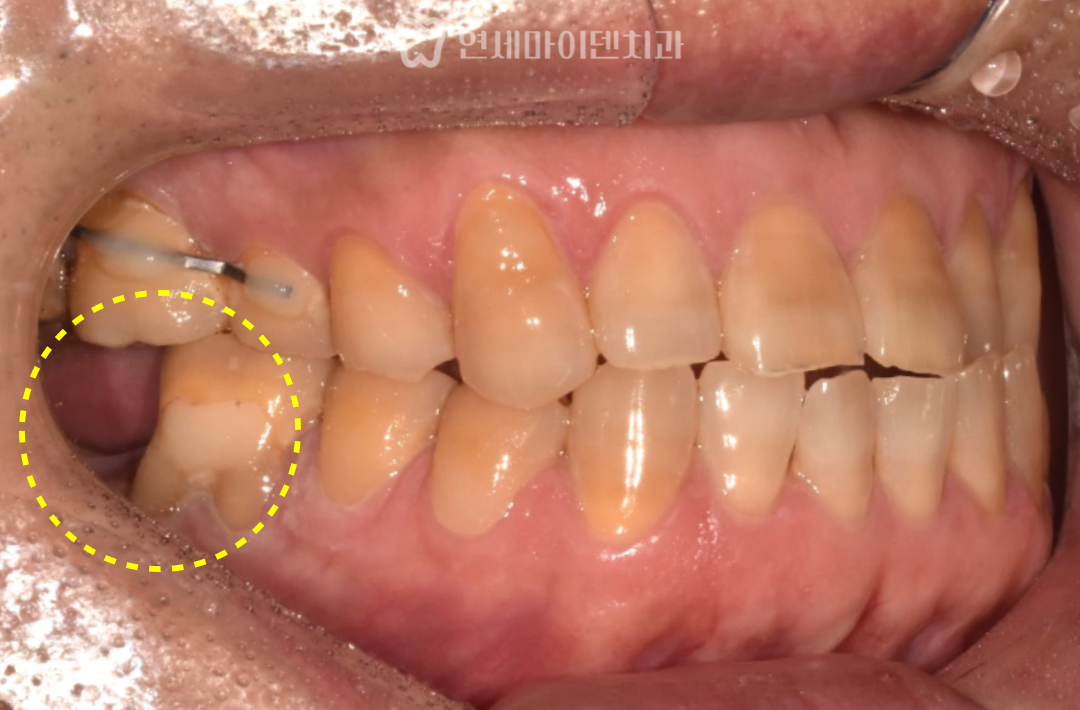

발치 후 상태와 문제점

환자분은 오랫동안 통증을 참고 지내다

결국 어금니 하나를 발치한 상태로 내원하셨습니다.

X-ray를 확인해보면,

반대편 어금니는 뼈 상태가 비교적 건강한 반면

문제 부위는 치조골 높이가

절반 가까이 무너진 상태였습니다

이 때문에 이전 병원에서는

“앞 치아도 곧 못 쓴다”며

두 개 모두 임플란트를 권유받았던 상황이었습니다.

하지만, 앞쪽 어금니의 경우

뿌리 앞쪽 뼈는 비교적 단단하게 남아 있었고

염증 범위도 제한적이어서

충분히 보존 가능성이 있는 상태였습니다.

즉,

무조건 두 개를 다 뽑아야 할 상황은 아니었습니다.

→ 위쪽 어금니가 내려오지 않도록

레진 + 와이어 스플린트 적용